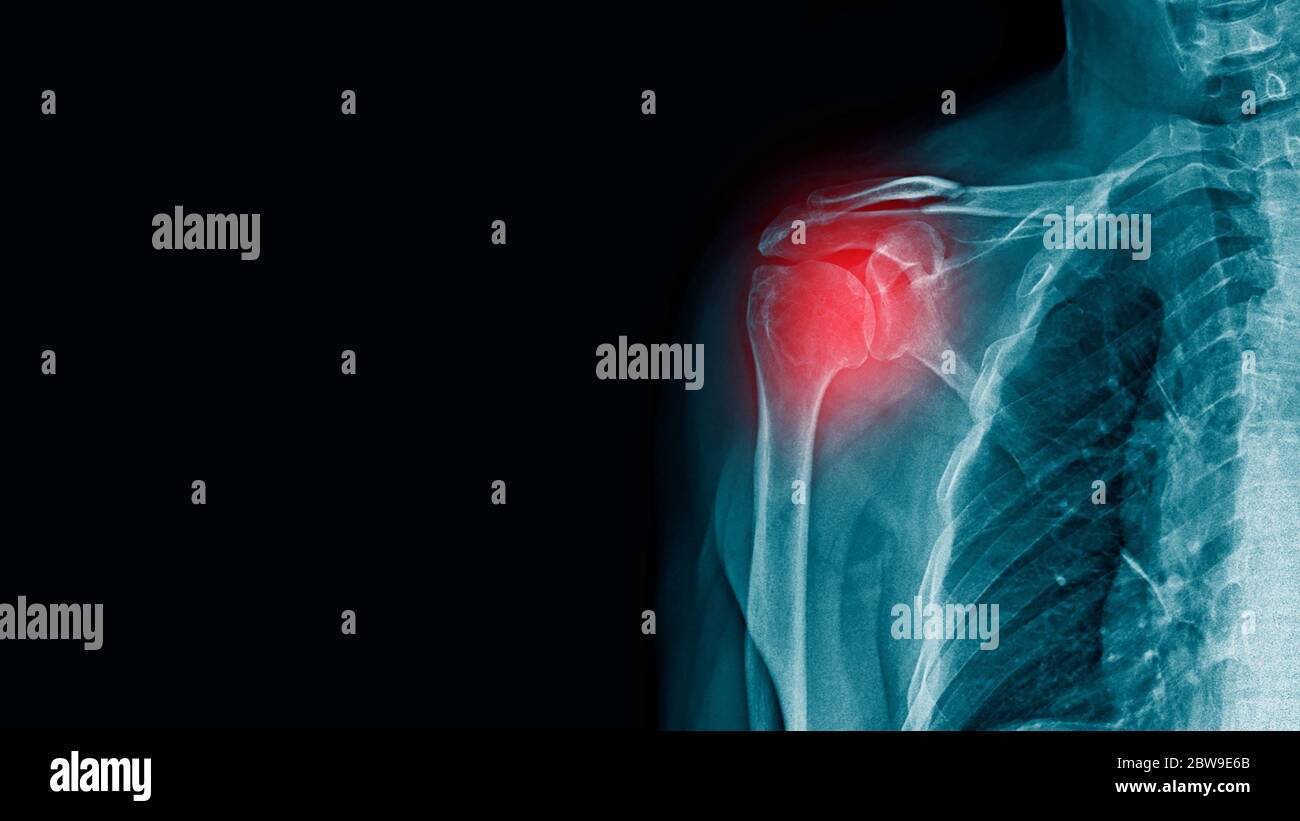

Xray Shoulder Joint Shoulder Front View for Diagnosis Fracture of Shoulder Fracture X Ray However, a doctor may request additional imaging, such as a ct. Soft tissue areas, cortical margins, trabecular patterns,bony alignment, joint. Magnetic resonance imaging (mri) : The shoulder joint is between part of the scapula or shoulder blade (blue line) and the proximal humerus (green line). A recommended systematic checklist for reviewing musculoskeletal exams is: The neer classification of proximal humeral. Shoulder Fracture X Ray.

Xray Shoulder joint shoulder transcapular view for diagnosis fracture Shoulder Fracture X Ray Soft tissue areas, cortical margins, trabecular patterns,bony alignment, joint. Magnetic resonance imaging (mri) : The neer classification of proximal humeral fractures is probably the most frequently used system along with the ao classification of proximal humeral fractures. However, a doctor may request additional imaging, such as a ct. A recommended systematic checklist for reviewing musculoskeletal exams is: The shoulder joint. Shoulder Fracture X Ray.